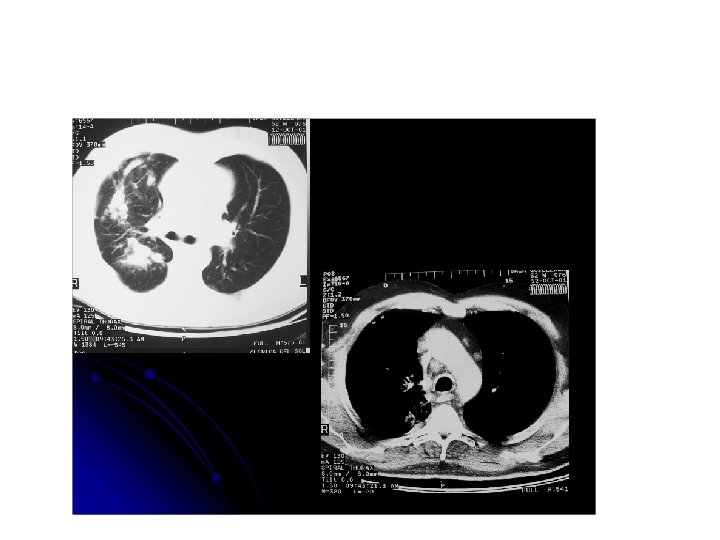

Se muestra nódulos en vertice izquierdo y ensanchamiento de mediastino.

El mismo pacinte con adenomegalias paratraqueales inferiores derechos y paraaórticos. Tambien se ven subaórticos e hiliares izqueirdas.